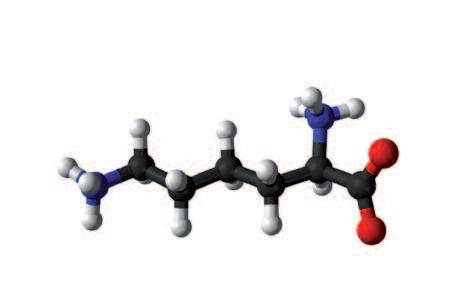

È interessante notare che la natura stessa ci fornisce due grandi gruppi di molecole che possono bloccare il meccanismo di dissoluzione del collagene. Il primo gruppo è rappresentato un blocco enzimatico intrinseco al corpo che può inibire l’azione degli enzimi proteolitici che digeriscono il collagene in pochi istanti. Il secondo gruppo di sostanze che bloccano gli enzimi proteolitici può essere presente nella nostra dieta eventualmente integrata. Il micronutriente più importante è l'aminoacido naturale L-lisina. Una quantità sufficiente di lisina, sotto forma di supplemento dietetico, può bloccare i siti di ancoraggio ai quali le collagenasi si legano alle molecole del tessuto connettivo. La lisina, quindi, impedisce a questi enzimi di dissolvere il tessuto connettivo in modo incontrollabile.

La lisina, un bloccante naturale di enzimi che digeriscono il collagene, deve essere fornita dalla dieta

La lisina occupa i ‘siti di ancoraggio’ in cui le collagenasi normalmente si legano alle molecole del tessuto connettivo in modo da digerirle. Una volta che la lisina occupa questi ‘siti di ancoraggio’, le collagenasi hanno meno presa sulle fibre di collagene e il degrado del tessuto è limitato

La lisina è un aminoacido essenziale, può inibire la digestione incontrollata del tessuto connettivo da parte delle cellule tumorali, inibendo così la diffusione delle cellule tumorali e della metastasi.

Tutte le funzioni metaboliche del corpo umano sono controllate dal linguaggio biologico. Una ventina di aminoacidi noti compongono tutte le proteine del nostro corpo. Questi blocchi formativi della vita funzionano come lettere dell'alfabeto. I nostri corpi utilizzano diverse combinazioni di amminoacidi per creare innumerevoli parole biologiche (peptidi) e frasi (proteine). I singoli aminoacidi (le lettere) hanno in sé anche importanti funzioni metaboliche individuali e la lisina ne è un ottimo esempio.

Le cellule del corpo possono produrre autonomamente la maggior parte degli aminoacidi. Questi aminoacidi sono chiamati ‘non essenziali’. Tuttavia ci sono nove aminoacidi noti che il nostro corpo non può produrre e che quindi devono essere forniti attraverso la dieta. Questi aminoacidi sono chiamati ‘essenziali’.

La lisina svolge un ruolo importante all'interno del gruppo di aminoacidi essenziali come la vitamina C lo svolge all'interno del gruppo delle vitamine. Il fabbisogno giornaliero di lisina supera quello di tutti gli altri amminoacidi. Tra le sue numerose funzioni, la lisina forma anche la struttura base della carnitina, che è importante per il metabolismo energetico di ogni cellula.

Il fatto che il corpo umano sia in grado di immagazzinare una grande quantità di questo aminoacido dimostra la sua importanza per la nostra salute. Circa il 25 per cento del collagene, la molecola più abbondante ed importante della struttura ossea, della pelle, delle pareti dei vasi sanguigni e di tutti gli altri organi, si compone di due aminoacidi: lisina e prolina. Quindi prendere una grande quantità di lisina non provoca effetti negativi in quanto il nostro corpo ha un’ottima familiarità con questa molecola e semplicemente espelle qualsiasi quantità superflua.

Atomi di azoto

Atomi di ossigeno

Atomi di idrogeno

1 nm (nanometro) = 1 milio nesimo di 1 millimetro (Moleco la di lisina è 10 000 volte più piccola di una cellula)

• Un corpo umano che pesa circa 70 kg contiene circa 10 kg di proteine.

• Il 50% di tale massa proteica è presente sotto forma di proteine d el tessuto connettivo, collagene ed elastina.

• Le lisina forma circa il 12% del collagene e dell’elastina, ovvero circa 1,3 kg

• Quindi un corpo umano che pesa circa 70 kilogrammi contiene circa mezzo chilo di lisina.

Dal momento che i nostri corpi sono abituati a grandi quantità di lisina, l'assunzione quotidiana di 12g di lisina, come integratore alimentare, ad esempio, per malati di cancro, non è considerata eccessiva.

L'attività degli enzimi che digeriscono il collagene può essere bloccato in due modi: con le molecole inibitrici del corpo (proteine enzimatiche) e con inibitori naturali forniti nella dieta, quali la lisina.

1. La lisina inibisce la distruzione del tessuto connettivo, impedendo la digestione enzimatica di molecole di collagene. Allo stesso tempo, questo aminoacido è una componente essenziale del collagene nel corpo

• La lisin a è un elemento importante della catena di aminoacidi e costituisce la molecola più importante del collagene. Poiché il nostro corpo non può produrre lisina, ogni singola molecola di lisina deve essere fornita dalla dieta o attraverso integratori alimentari.

Unità fondamentale del collagene, assunta esclusivamente tramite l’alimentazione